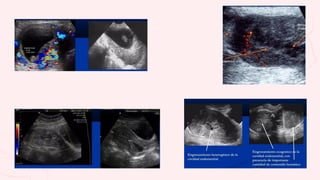

Se localizan restos en cavidad uterina y canal

vaginal. El endometrio mide >15mm

Expulsión total del producto, el endometrio

mide <15mm

• #15 Aborto diferido: imagen superior izquierda: al doppler color no se aprecia vascularidad y no hay FCF Imagen superior derecha: restos ovulares Imagen inferior izquierda: aborto en evolución, se ve apertura cervical y presencia de saco